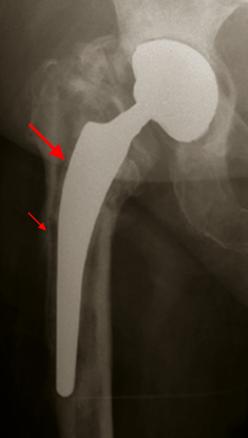

Grande flèche : liseré d'ostéolyse avec descellement de la hampe fémorale.Petite flèche : appositions périostées.